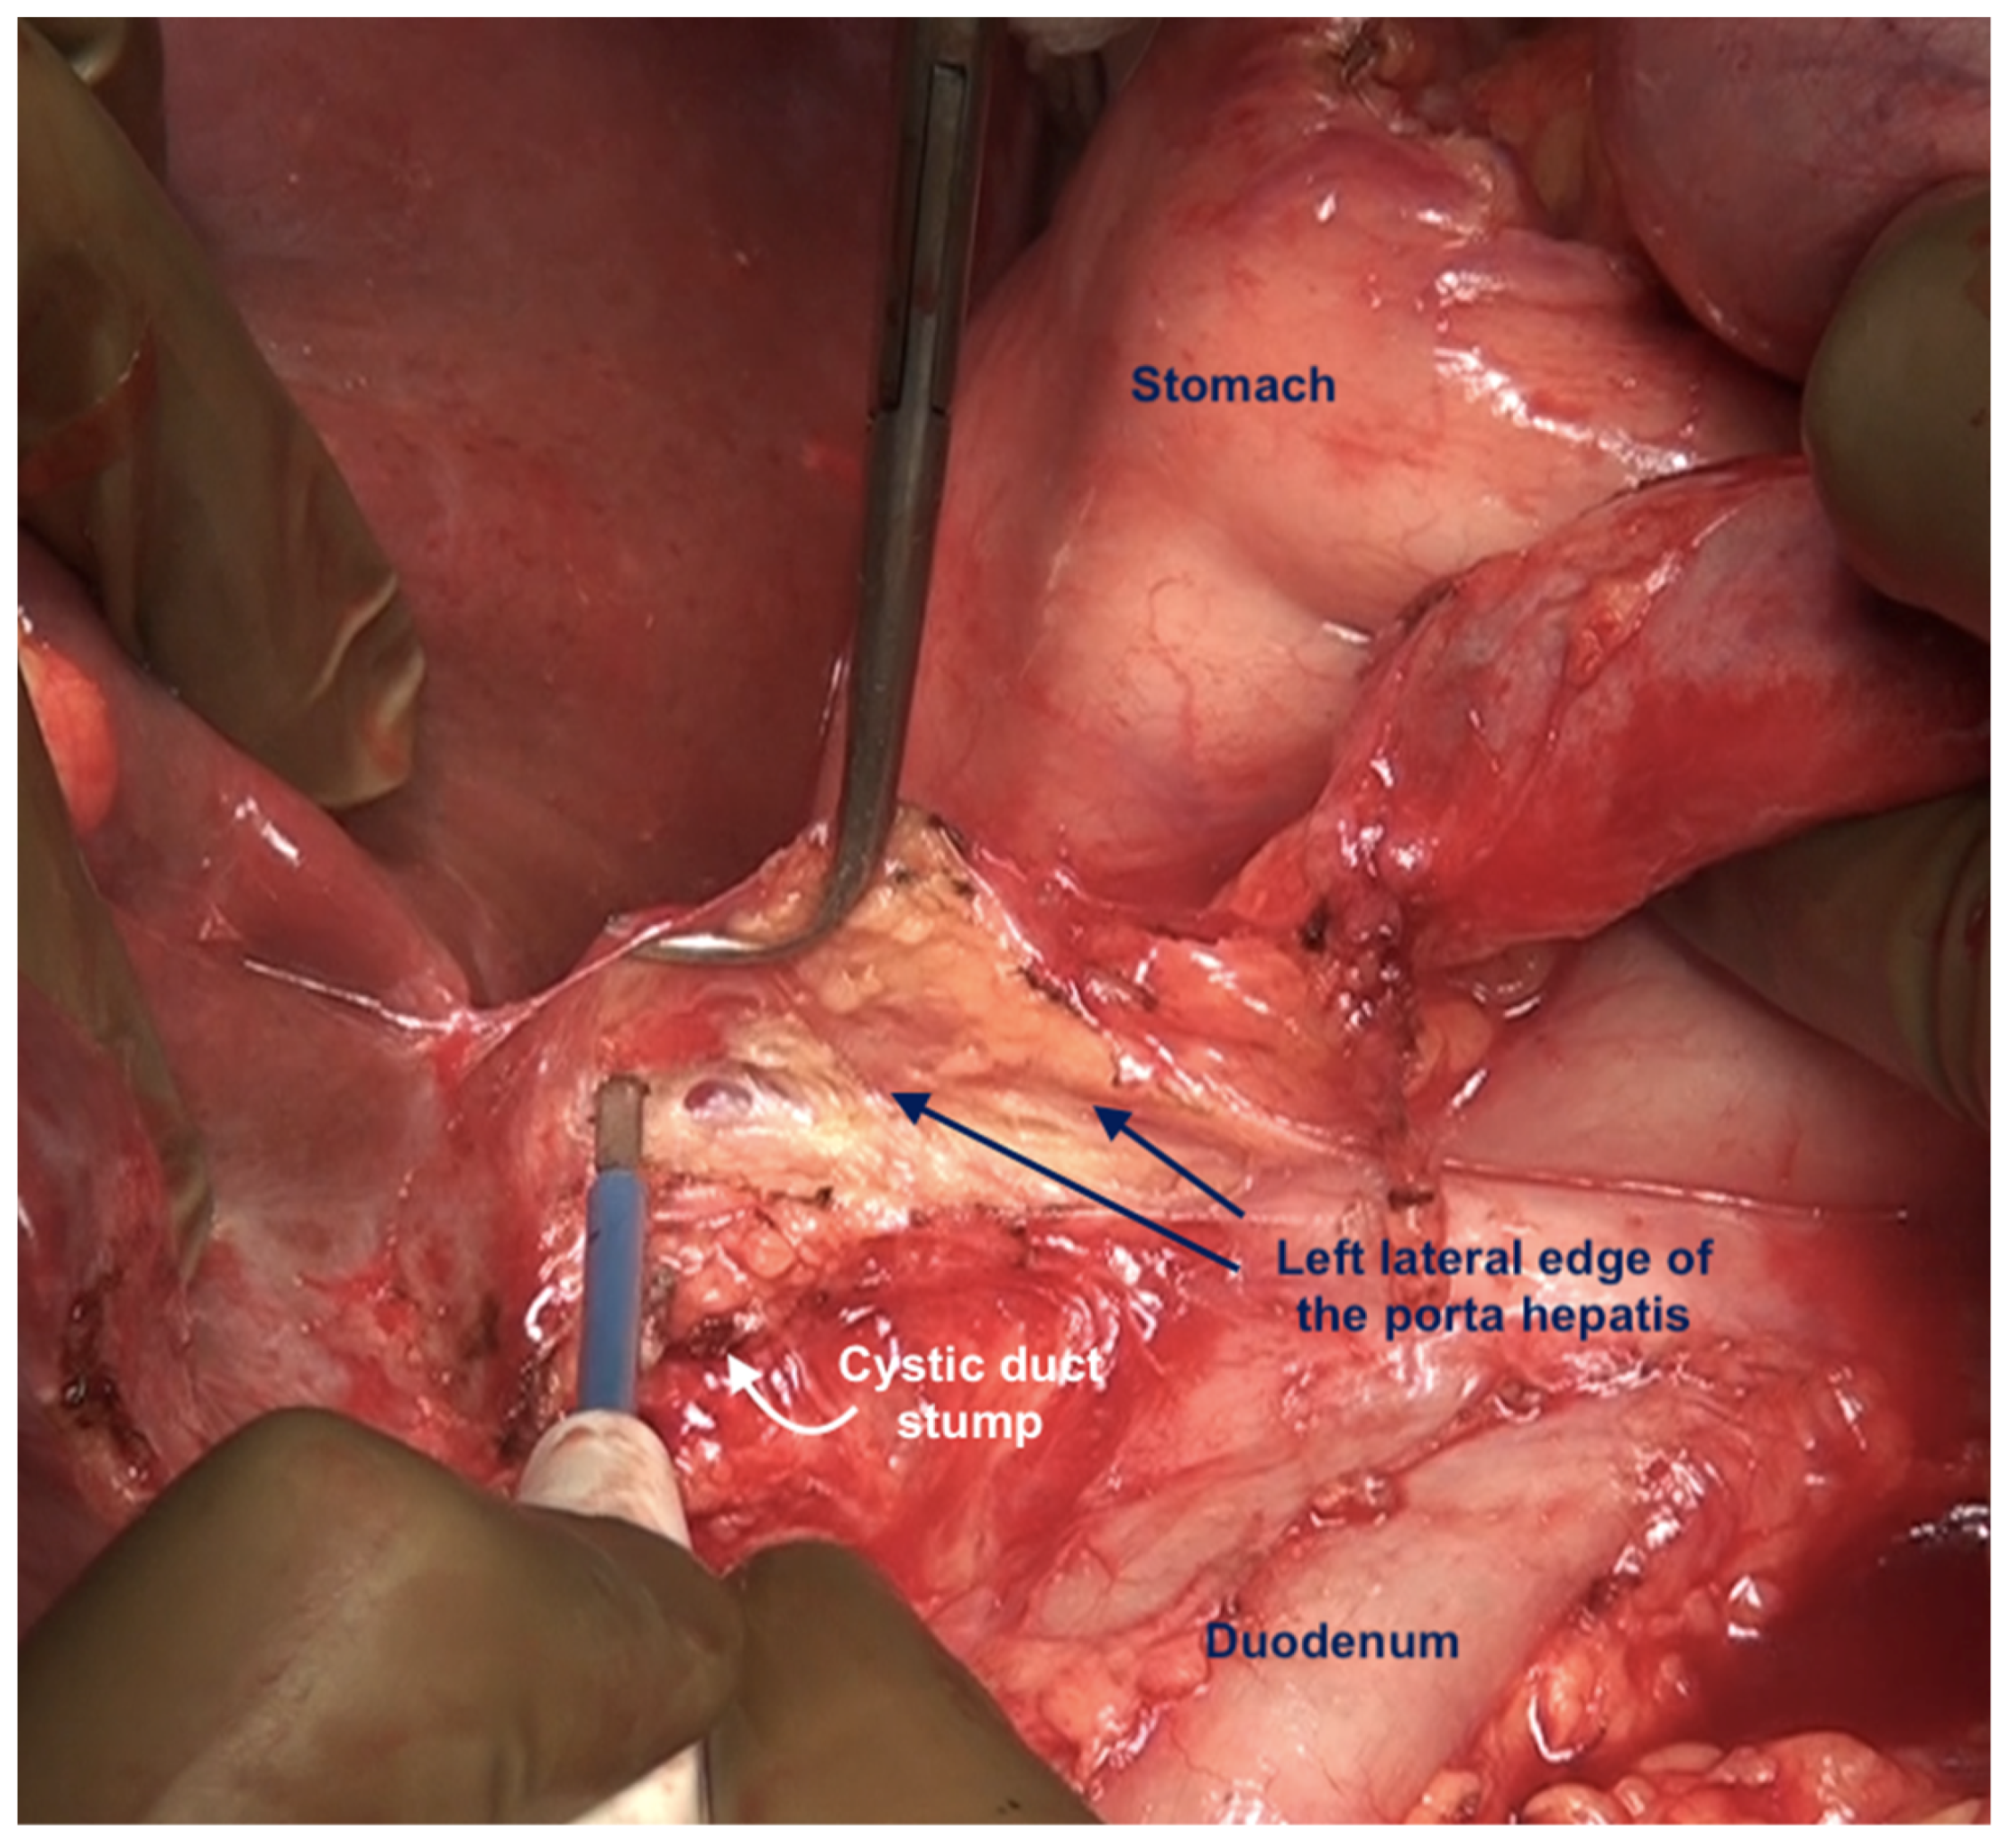

The clearance of the hepatoduodenal ligament begins with a cholecystectomy [43]. The peritoneal fold covering the gall bladder is a common disease site (Figure 20).

Figure 20.

Tumor deposits on the serosa of the gall bladder. The peritoneal fold between the gall bladder and the duodenum has to be divide to visualize this disease.

The fundus first approaches the gall bladder by dissecting the cystic artery and the cystic duct and dividing them. The peritoneum over the gall bladder is maintained intact and then retracted over the portal structures, which are carefully dissected using blunt or monopolar or bipolar dissection (Figure 21) [67]. When there is an extensive disease, the cystic duct can be used to identify the correct plane. The fat around the portal structures should be preserved (Figure 22). Variations in the anatomy of the portal structures should be considered. The lesser omentum could be removed in continuity or separately.

Figure 21.

Resection of the hepatoduodenal ligament in progress.

Figure 22.

The porta hepatis after complete dissection of the anterior layer of the hepatoduodenal ligament. The fat around the portal structures is preserved.